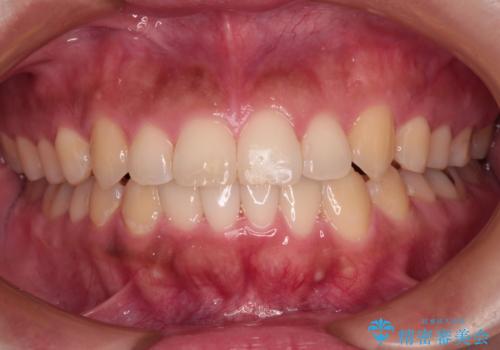

【モニター】カリエール・ディスタライザーを併用した八重歯のインビザライン矯正

カリエールディスタライザーを併用したことで、すっきりとした口元になり、上下の正中を合わせることができました。